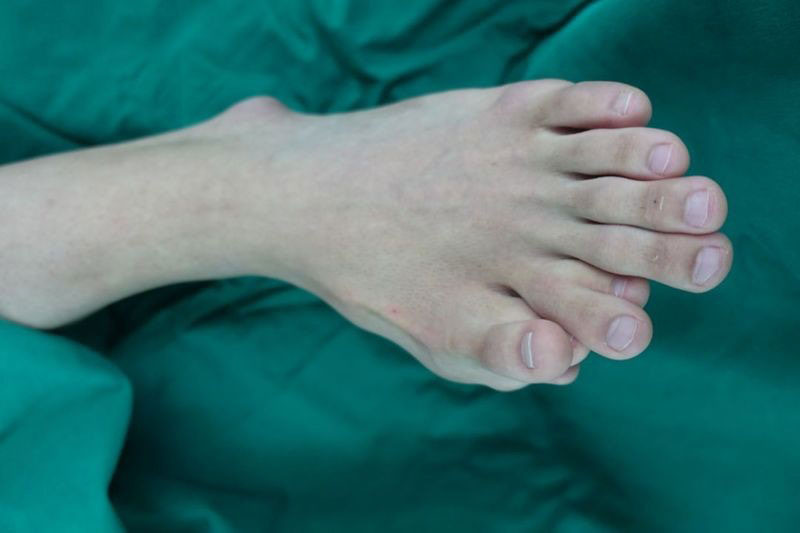

เมื่อวันที่ 31 ตุลาคม 2562 เว็บไซต์เดลี่เมล เผยเรื่องราวของ อาจุน (Ajun) หนุ่มวัย 21 ปี จากเมืองหลูเฟิง ทางตอนใต้ของจีน เขาเกิดมาพร้อมความผิดปกติ เท้าข้างหนึ่งมีนิ้วเท้างอกเกินมา 4 นิ้ว รวมเป็น 9 นิ้ว ทำให้ต้องใช้ชีวิตแสนยากลำบาก และคิดว่าตัวเองเป็นคนไม่สมประกอบมาตลอด

ในที่สุด เมื่ออาจุนเข้าสู่วัยผู้ใหญ่ สามารถตัดสินใจได้ด้วยตัวเอง เขารีบขอความช่วยเหลือทางการแพทย์ ซึ่งเมื่อแพทย์ทำการเอกซเรย์พบว่า ความผิดปกติมีความรุนแรง นิ้วเท้าขนาดเล็กงอกแทรกระหว่างนิ้วเท้าปกติในลักษณะแปลก และเขาไม่มีนิ้วโป้ง กลับแทนที่ด้วยนิ้วสองนิ้วเป็นรูปตัววี